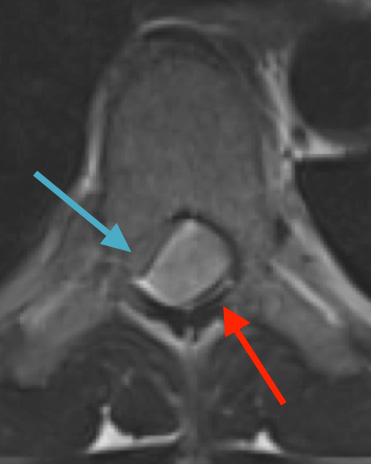

Preoperative MRI T2 demonstrating obstruction of CSF around the cord (blue arrow), resulting from the tumor (red arrow)